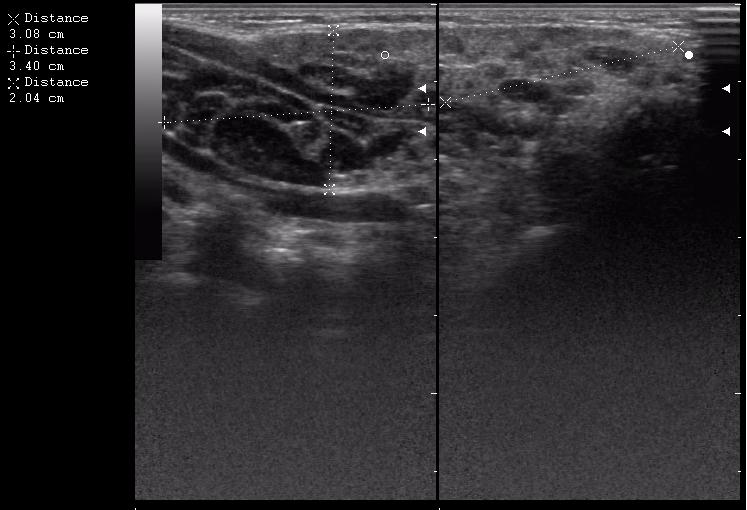

размер железы 30,8 + 34 = 64,8 мм х 20,4 мм